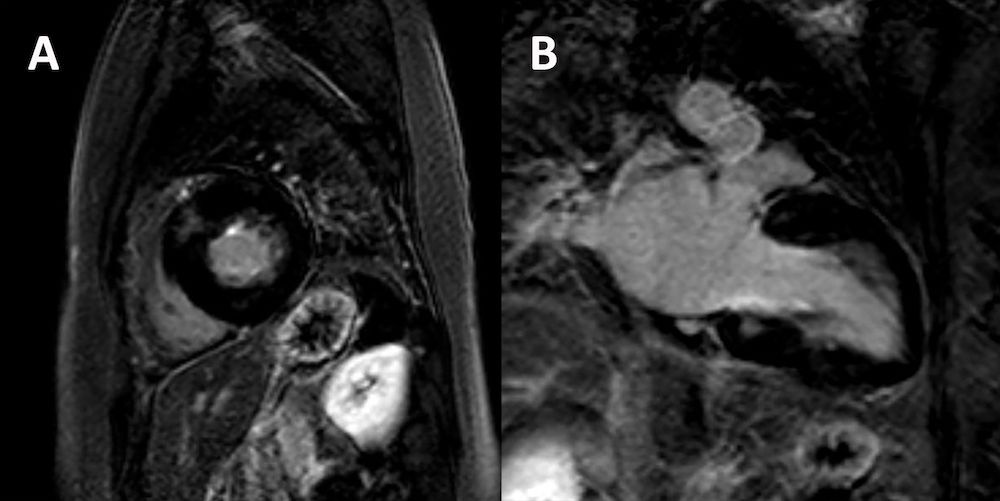

¿Cómo es una miocardiopatía hipertrófica? ¿Qué tipos existen? buff.ly/2yDwY4O Repaso del capítulo "Miocardiopatías" de nuestra Biblioteca de Preguntas Básicas de Imagen Cardíaca

¿Cómo es una miocardiopatía hipertrófica? ¿Qué tipos existen? buff.ly/2yDwY4O

Repaso del capítulo "Miocardiopatías" de nuestra Biblioteca de Preguntas Básicas de Imagen Cardíaca